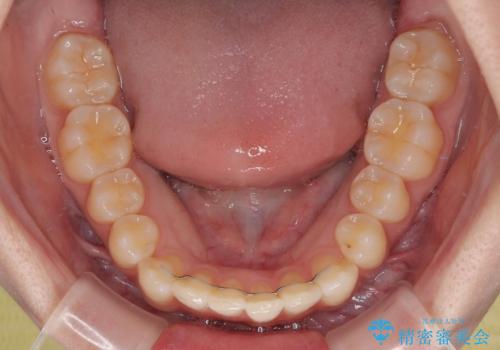

- 上下前歯の重なりを気にして来院された患者様です。

安価なインビザラインパッケージを用いての治療を希望されており、デコボコの程度が中等度であったため、インビザライン・モデレートを用いて矯正治療を行うこととしました。